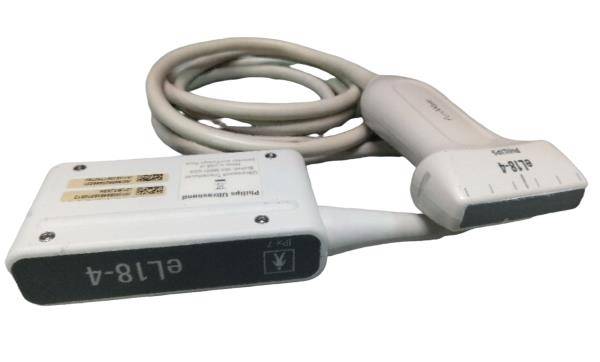

Seller Notes:âTested using a Logiq P5 Ultrasound unit. Plugs into ultrasound and produces image. Image has dead zones and white bars inconsistent with other functional transducers (pictured). Show signs of use. Includes everything shown. Sold AS IS.â

Brand: GE

Model: 4C